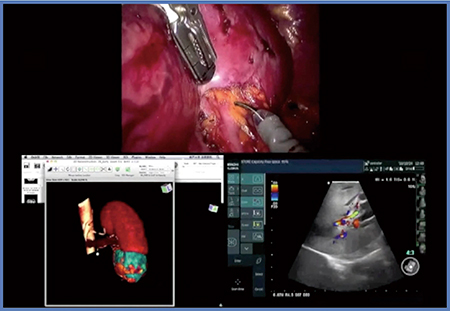

症例2は,44歳,女性,左腎細胞がんで,RNSは9aである(図3)。腎下極の大半を置き換えるほど大きな腫瘍(T1b)で,経腹膜アプローチにてRAPNを施行した。ドプラ画像(図3右下)では,腎門からの血管が腫瘍に対してどのように走行しているか,あるいは動脈の位置などを確認可能である。本症例は腫瘍が大きいため,マーキングは水平方向と前額断の両方で行うが,プローブに目盛りがあるため,腫瘍の境界を理解しやすい。それを基に切除のイメージを膨らませつつ,時間をかけて全周のマーキングを丹念に行った。本症例は切除断端陰性で,出血は50g,阻血時間は25分であった。

図3 症例2:RNS 9aの左腎細胞がん(44歳,女性)